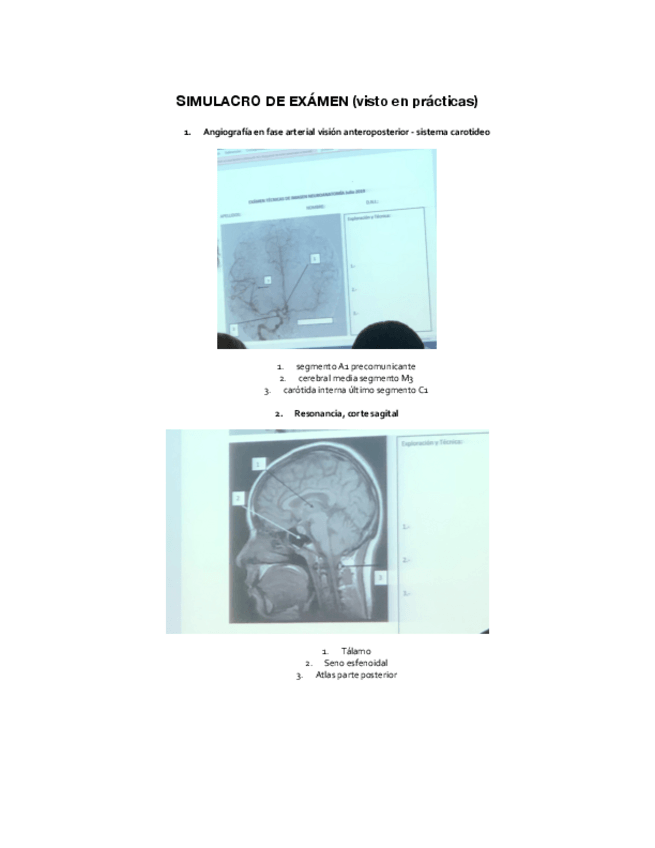

imágenes y respuestas del simulacro de examen que hicimos en la práctica de angiografías de ATI

2 páginas